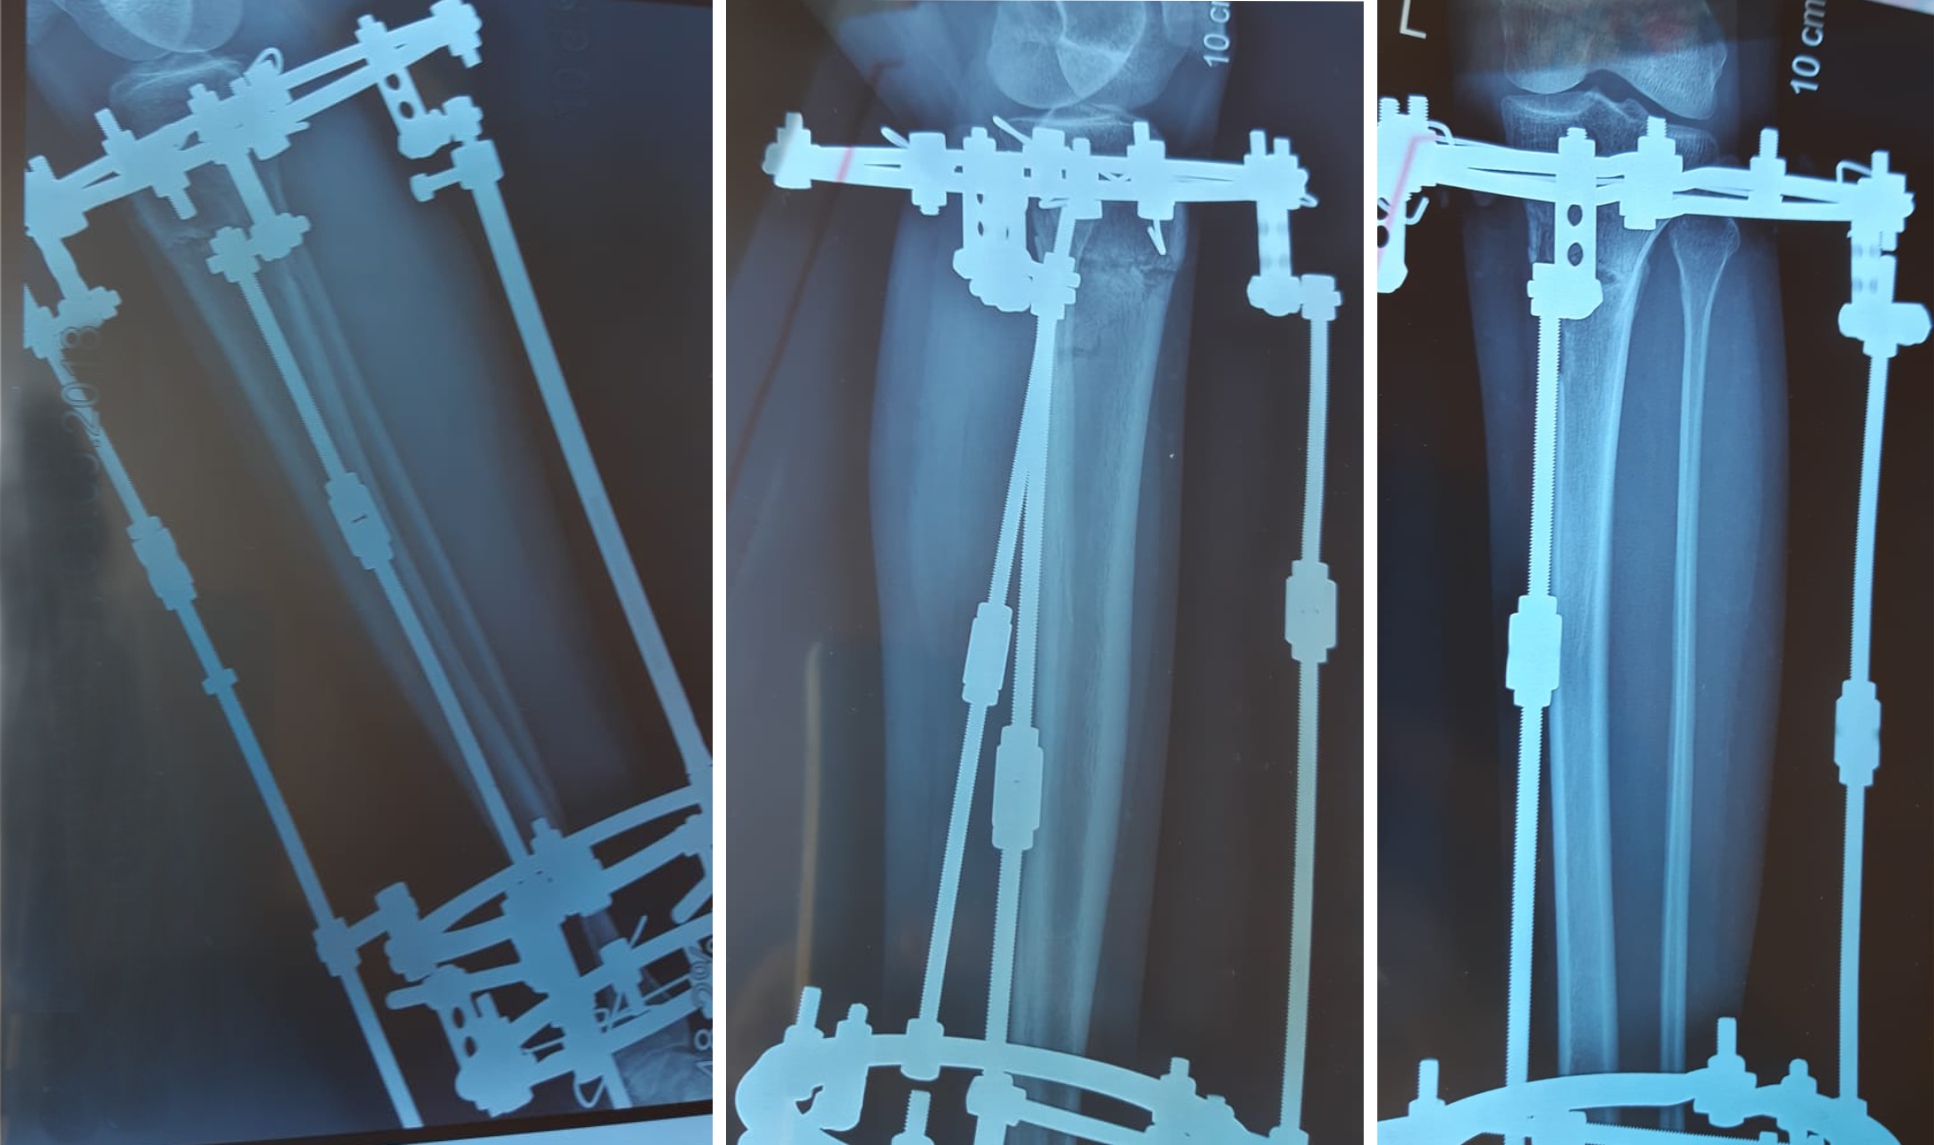

перед крутками.

IMG-20180713-WA0022.jpg

В процессе круток.

У пациентки имеется Ротация.

20180719_153144.jpg